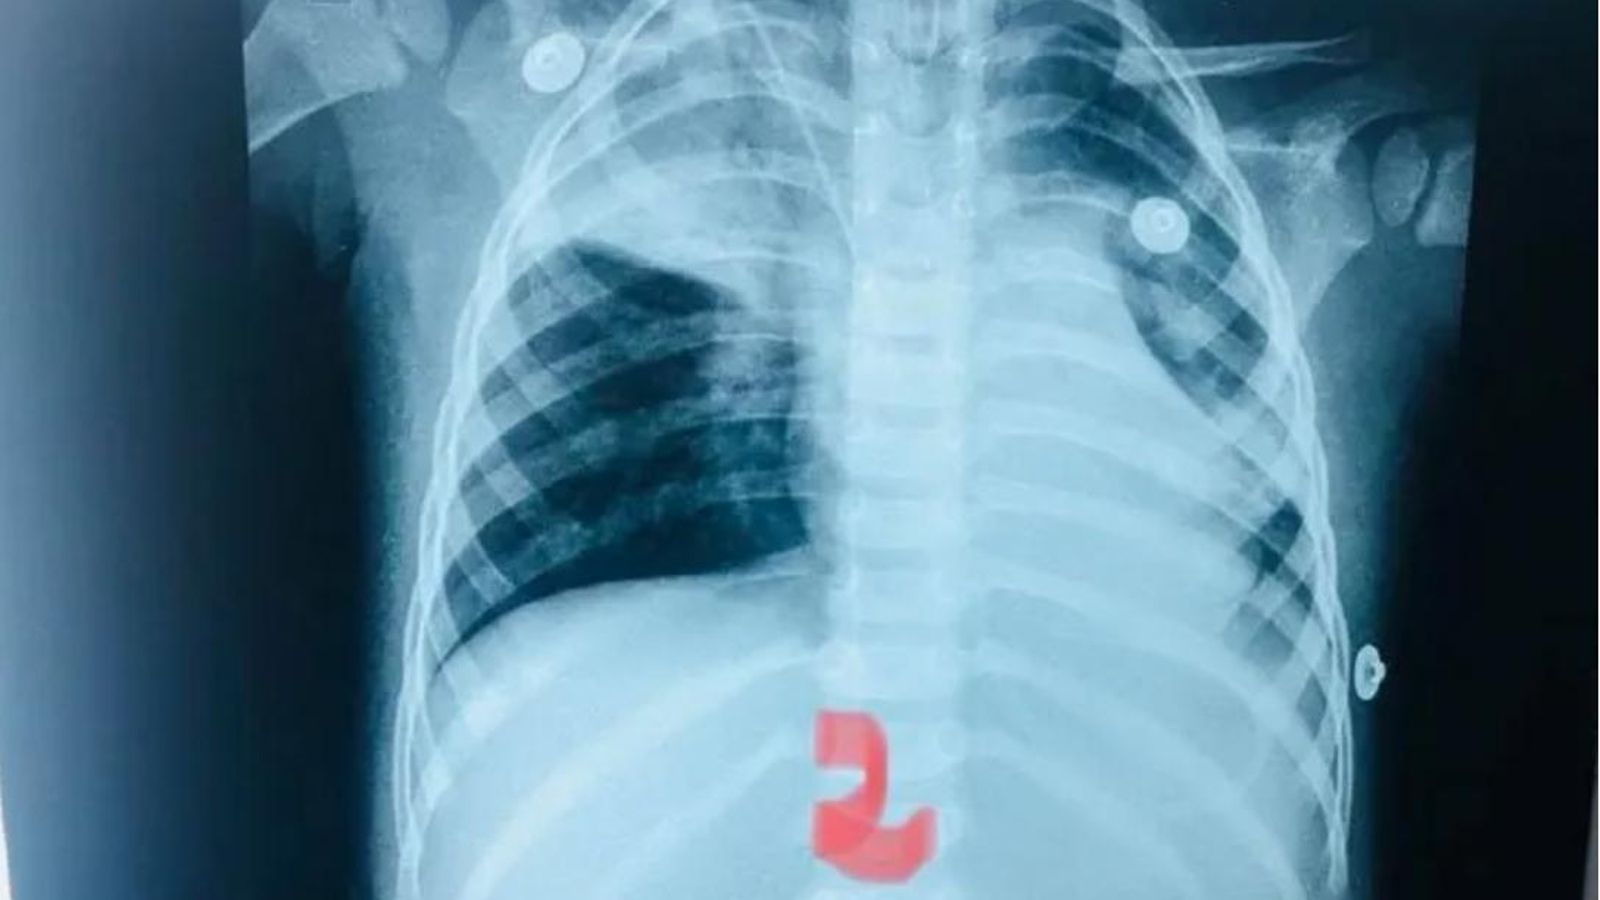

El niño comenzó a tener una tos intensa, lo que llamó la atención de la madre, que se percató de que su hijo rápidamente comenzó a ponerse morado y casi no respiraba, por lo que decidió llevarlo de inmediato al hospital. El neumólogo Carlos Morínigo, quien asistió al niño de 2 años, informó que la asfixia fue causada por esta semilla que se alojó en el pulmón (lado derecho) del pequeño.

Al llegar al hospital, los médicos confirmaron que la semilla provocó un paro respiratorio, por lo que tuvieron que reanimarlo e intubarlo. Rápidamente ordenaron que sea derivado al Instituto Nacional de Enfermedades Respiratorias y del Ambiente (Ineram), en Asunción, donde evolucionó favorablemente.

Asimismo, durante toda la intervención, el pequeño tuvo que ser atendido con asistencia respiratoria artificial ya que no respiraba por sí mismo. En mitad de la exploración, la semilla se movió al otro pulmón, lo que pudo haber sido fatal, ya que le causó un cuadro de neumonía muy grave. El infante sobrevivió de 'milagro' y gracias a una rápida intervención (dada la cercanía del hospital).